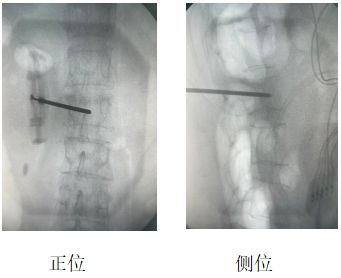

患者辛某(化名),女性,69歲,因“腰部劇烈疼痛伴活動(dòng)受限2天”入院。既往有骨質(zhì)疏松癥病史,影像學(xué)檢查提示L2椎體新鮮壓縮性骨折,VAS評(píng)分8分。

當(dāng)?shù)蒯t(yī)院建議外科手術(shù)治療,患者及家屬拒絕開刀手術(shù),遂來我院疼痛科。結(jié)合患者自身情況,劉康主任與科室人員經(jīng)討論,決定行“經(jīng)皮椎體成形術(shù)(PVP)”聯(lián)合“脊神經(jīng)后內(nèi)側(cè)支射頻調(diào)控術(shù)”,同時(shí)解決椎體穩(wěn)定性與神經(jīng)源性疼痛問題。